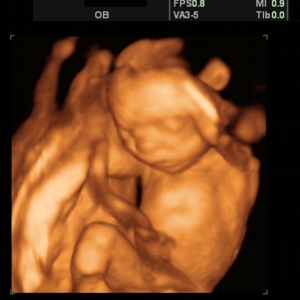

Трехмерное УЗИ – это более новый метод исследования, который позволяет увидеть на мониторе «фотографию» еще не рожденного ребенка. Четырехмерное УЗИ – это еще более сложный и совершенный метод исследования, который позволяет наблюдать за трехмерным изображением плода в движении. Таким образом, 3D УЗИ можно сравнить с фотографией, а 4D УЗИ с видеосъемкой.